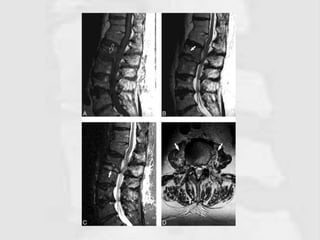

Figure 2: Sagittal T2 (a) and T1 (b) with coronal T2 (c) and transverse (d and e) magnetic

resonance images dorsolumbar spine of the patient showing two oval cysts measuring

10 cm × 9 cm × 5 cm contained multiple round grape bunch-like daughter cysts, in the

right pre- and para-vertebral region along with erosion of the right half of D8 and D9.

The cysts are hypointense in T1 and hyperintense in T2 sequences

Figure 2: SagittalT2 (a) and T1 (b) with coronal T2 (c) and transverse (d and e) magnetic resonance images dorsolumbar spine of the patient showing two oval cysts measuring 10 cm × 9 cm × 5 cm contained multiple round grape bunch-like daughter cysts, in the right pre- and para-vertebral region along with erosion of the right half of D8 and D9. The cysts are hypointense in T1 and hyperintense in T2 sequences http://www.jotr.in/article.asp?issn=0975- 7341;year=2017;volume=9;issue=2;spage=134;epage=138;aulast=Jain